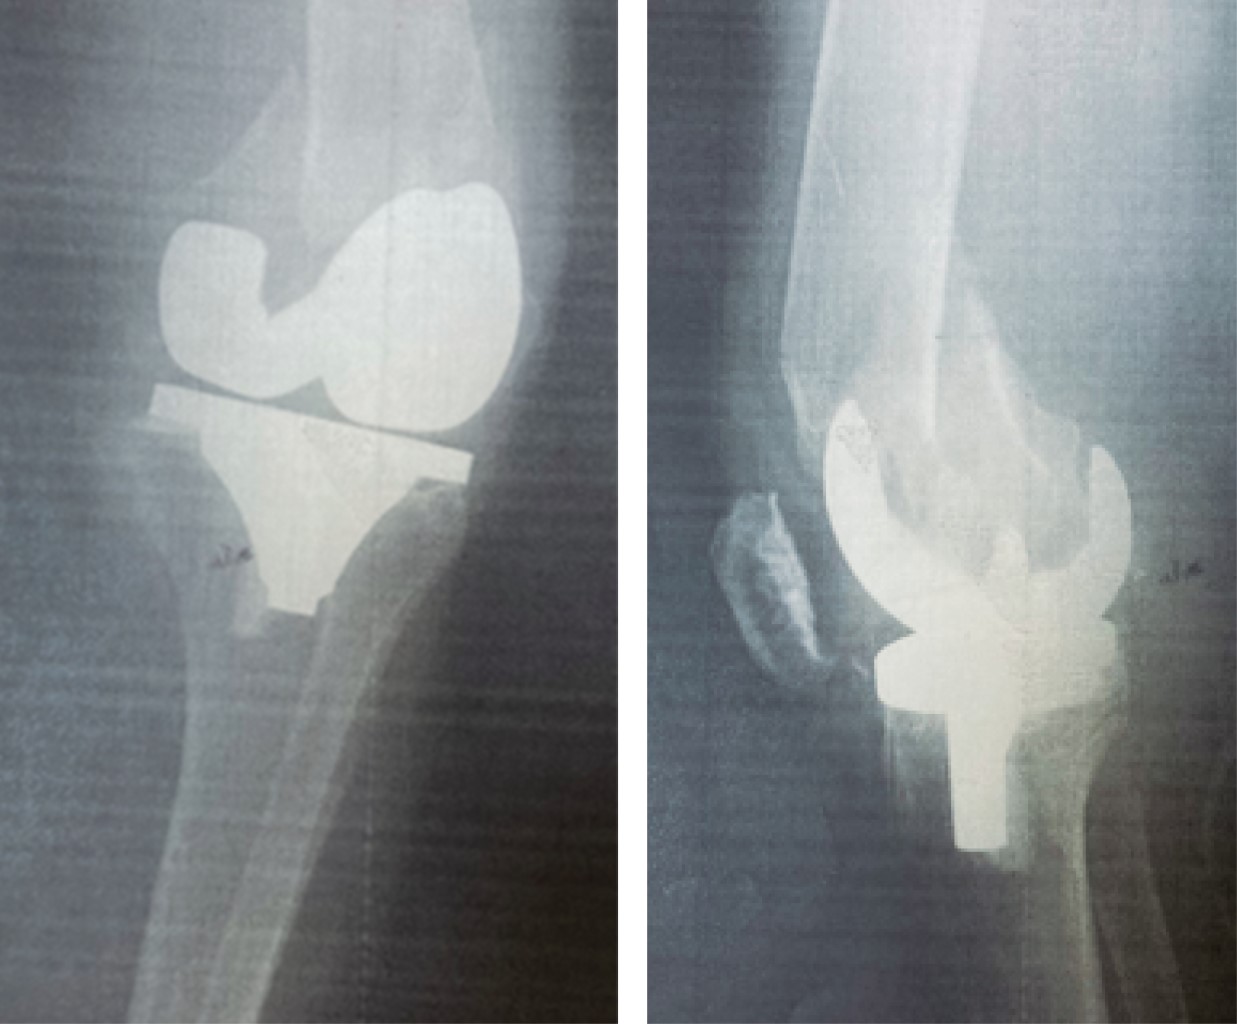

Figure 1